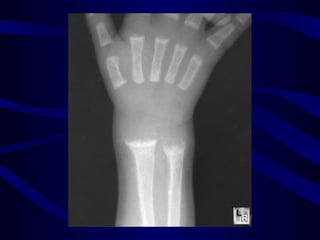

X - rays

Osteomalacia

• Osteopenia

• Looser zone ,

• biconcave vertebra ,

• Spontaneous fractures

Pseudofractures

X - rays Osteomalacia •Osteopenia • Looser zone , • biconcave vertebra , • Spontaneous fractures